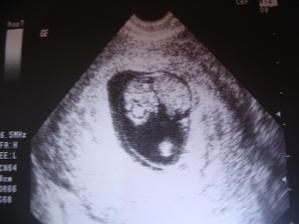

27.11.2009 na testíku jsem objevila vysněné krásné //, tak doufáme, že všechno dobře dopadne a my budeme mít kolem 7.8.2010 další miminko a Verunka bratříčka nebo sestřičku. Na UTZ jdeme 10.12.2009, přesně na Verunčiny 2.narozeniny, tak snad nám to přinese štěstí a bude všechno tak jak má být. ...... 5.12.2009 čárka na testíku opět krásně zesílila, tak snad je zatím všechno v pořádku....... 8.12.2009 - poslední testování, čárka už nemá kam sílit 🙂. Nevolnosti se stupňují ☹ ........ 10.12.2009 - dnes jsou Verunce 2 roky !!!. Byli jsme na UTZ a ten dopadl výborně, byla vidět dutinka a plodové vejce se žl. váčkem. Na srdíčko bylo ještě moc brzy, takže si UTZ zopákneme ještě 22.12. 🙂